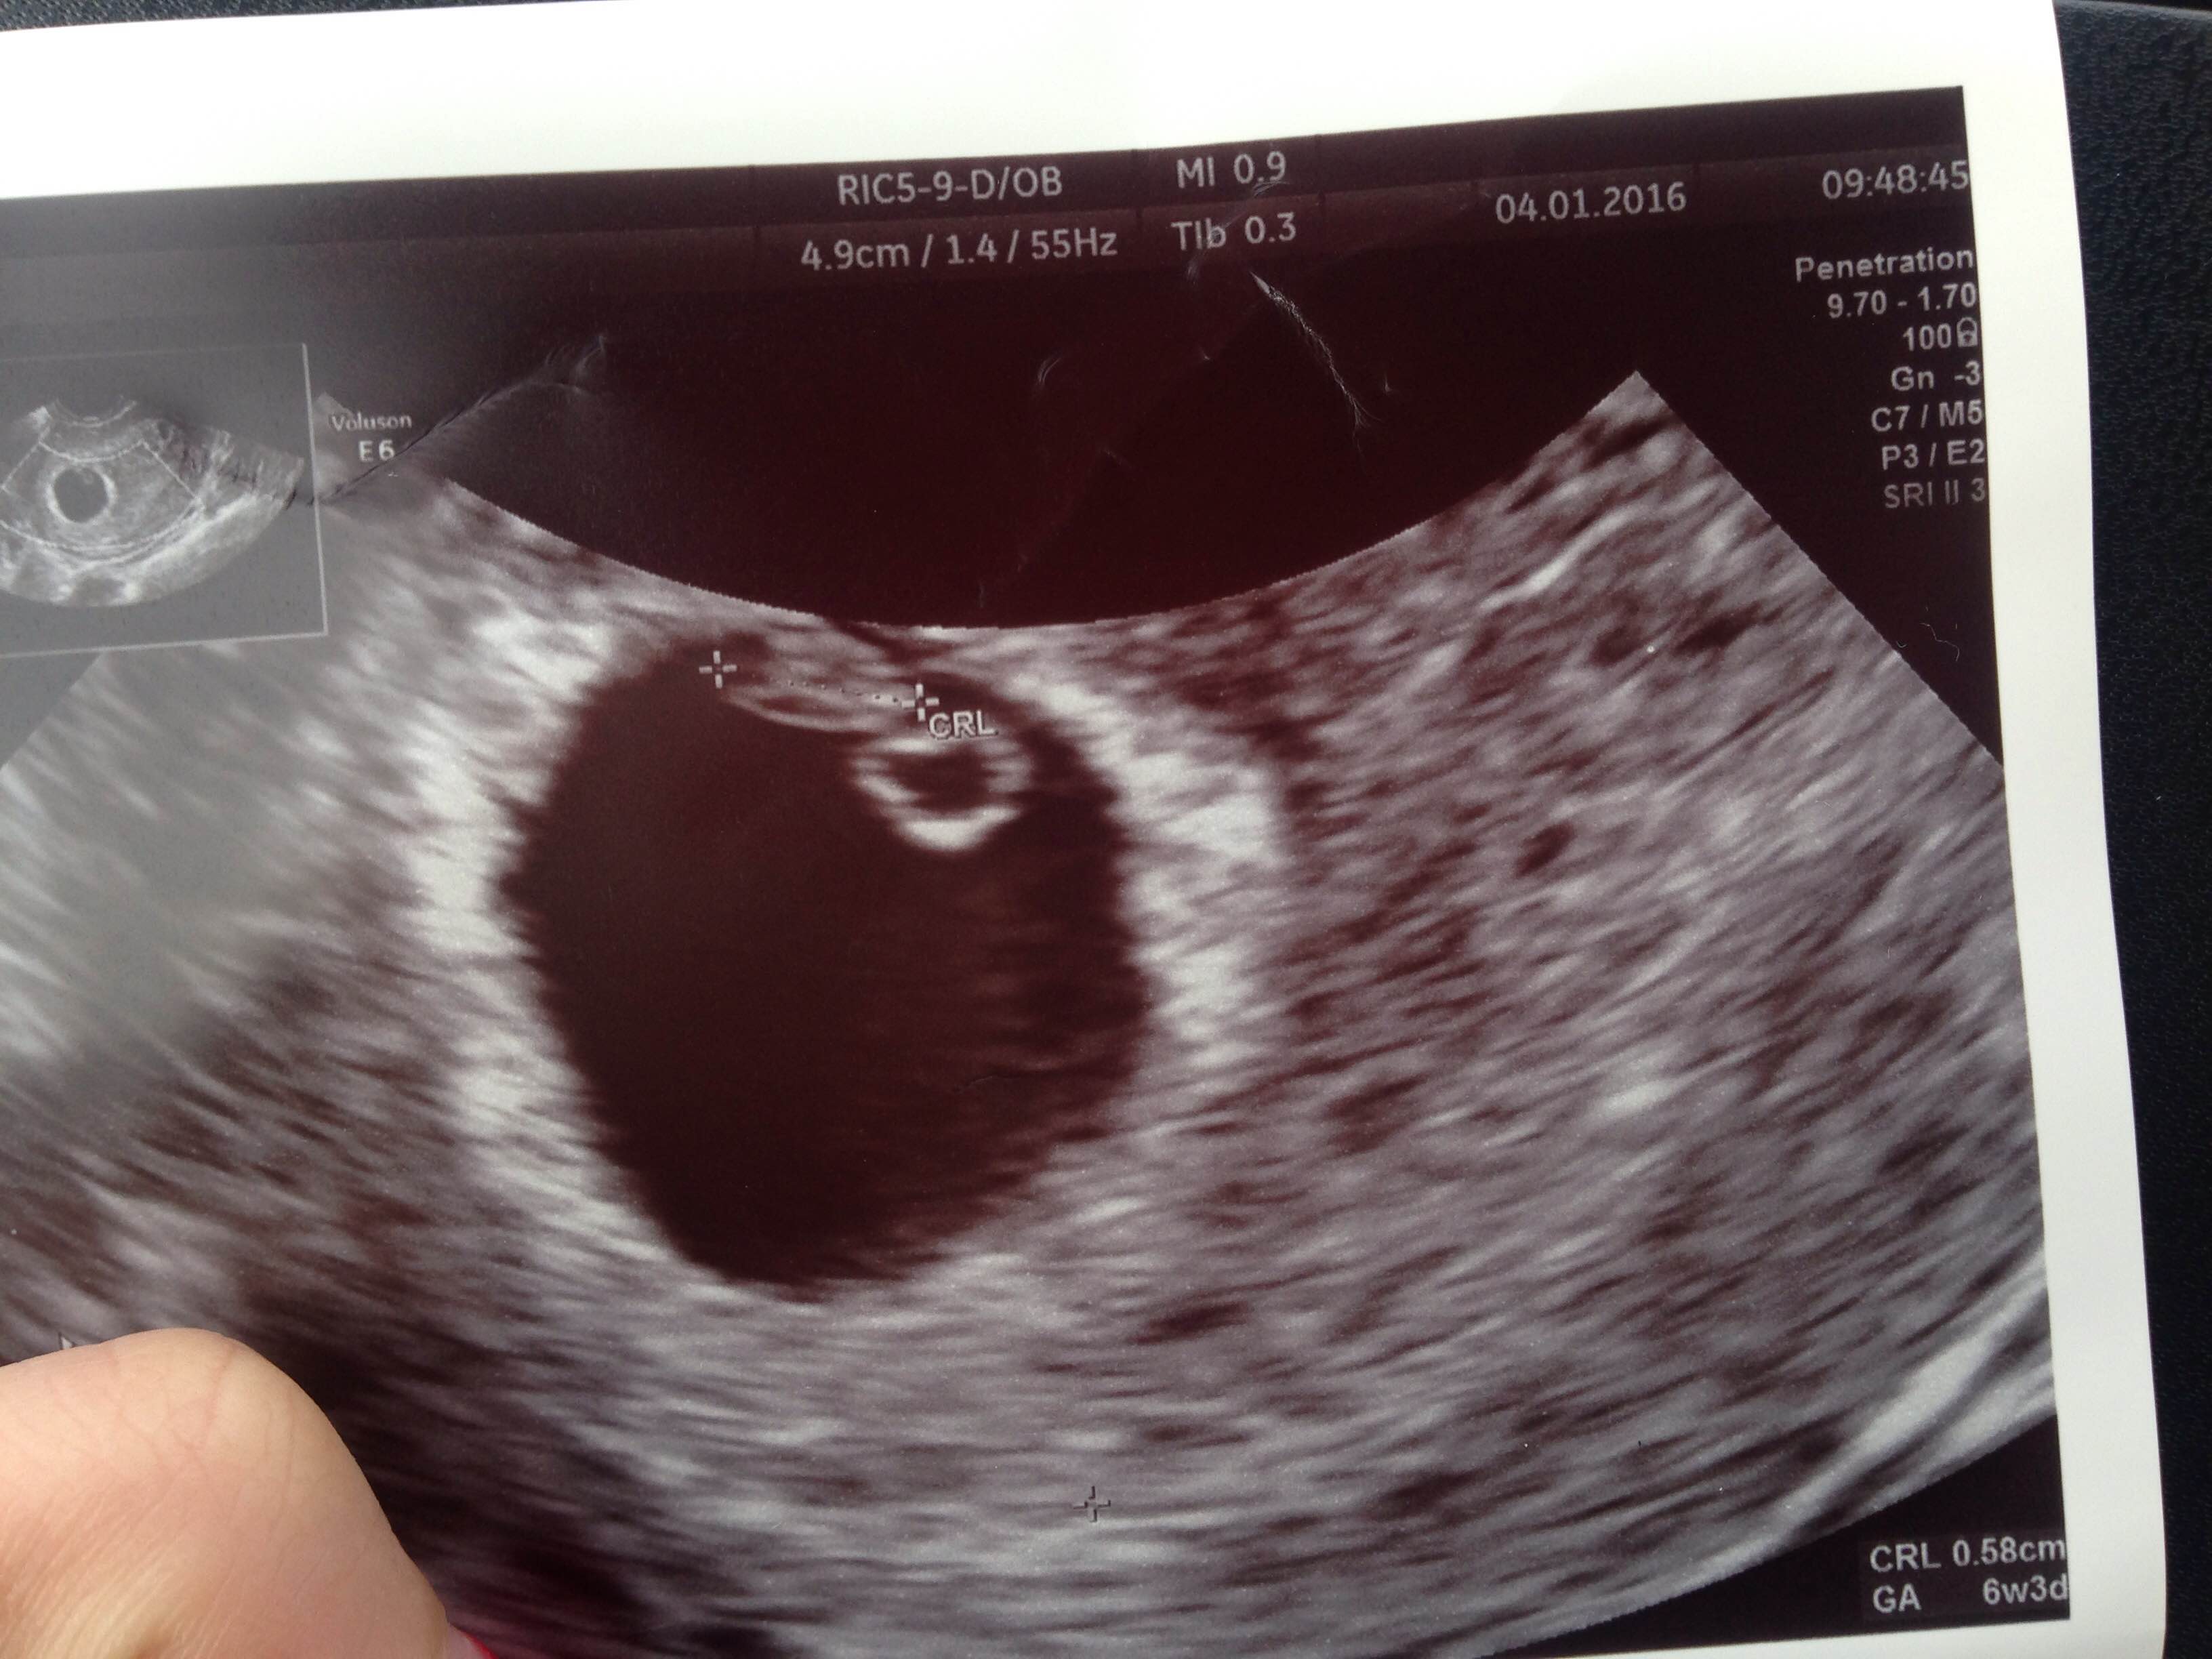

Byłam dzisiaj na usg i pierwszy raz widziałam swoją fasolkę i bijące serduszko :) ma 5,8 mm, gin powiedziała ze rozwija się prawidłowo. 6t3d wg usg.

Byłam dzisiaj na usg i pierwszy raz widziałam swoją fasolkę i bijące serduszko :) ma 5,8 mm, gin powiedziała ze rozwija się prawidłowo. 6t3d wg usg. Zobacz załącznik 741083